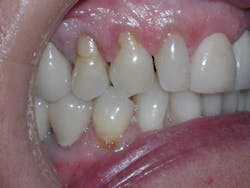

Figure 3

Sandra is a common example of a patient having a malocclusion that is the direct cause of her recession, and abfractions. When we first examined Sandra, her chief complaint was her smile (see Figure 3). She was unhappy with her smile and "crooked" teeth and had the desire to fix them.

Sandra expressed to us that she looked into clear aligner therapy but was told she was not a candidate. She was told she would need two years in braces and possibly some teeth extracted. These treatment options were undesirable, so she chose to do nothing. We assured her that she was an excellent candidate for clear aligner therapy, and her treatment time would be 14 months with no extractions.

At the consultation, Sandra's photos were used to teach. The photo of the lower crowding with the lingual plaque and calculus was used to teach Sandra the difference between crowded teeth and aligned teeth. We also informed her that her teeth are not actually "crooked" (her chief complaint). The mandibular occlusal view pointed out her V-shaped arch provided no room for her teeth to fit within the arch.

The remaining photos were used to teach the difference between a good bite and a bad bite. Sandra learned about clefting, recession, abfractions, and the visible areas of enamel wear on multiple teeth. Sandra understood that clear aligner therapy would change her bad bite to a good bite, resulting in a beautiful, healthy smile. My goal went further than that. I knew the benefits of aligned teeth include increased longevity, a healthy periodontium, and proper occlusion for her to enjoy a lifetime of oral health.